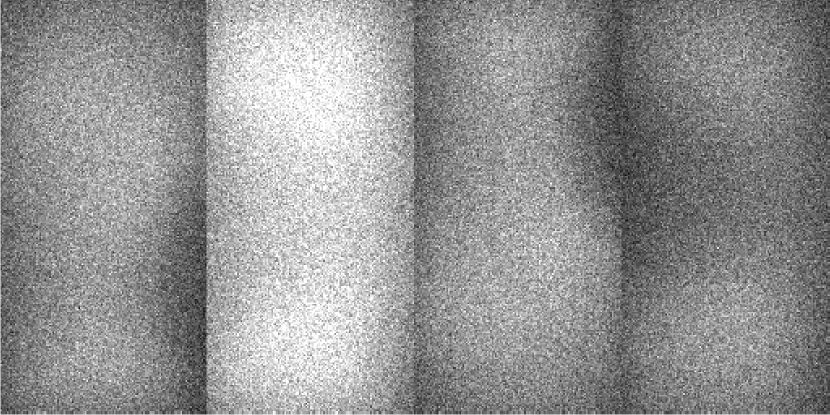

For illustrative purposes, select scatter estimates, along with the ground-truth are shown in Figure 4.

Refer to caption

(a) Oracle scatter

(b) Uniform estimate

(c) SKS estimate

(d) ASKS estimate

(e) Online-prior-MC

(f) Offline-prior-MC

Figure 4: Examples of low-dose scatter estimates shown with grey scale [10,70]: (a) is the oracle scatter from the measurement synthesis; (b) is a uniform estimate; (c) and (d) are SKS and fASKS estimates respectively; (e) and (f) are on-line and off-line planning MC estimates respectively.